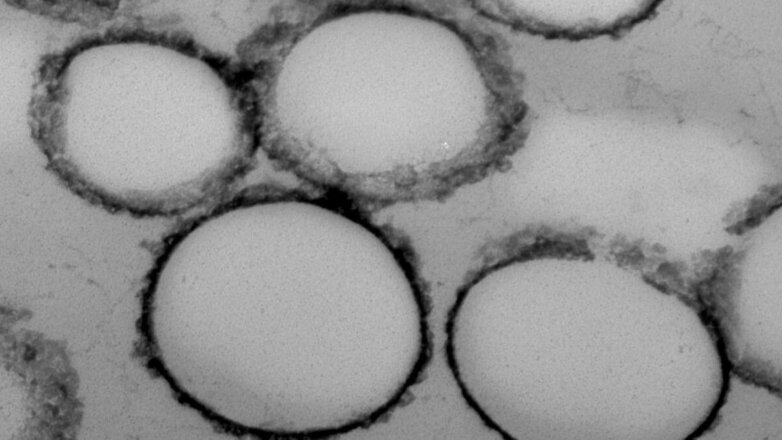

Рак в ранней стадии стало проще выявить благодаря уникальным наночастицам